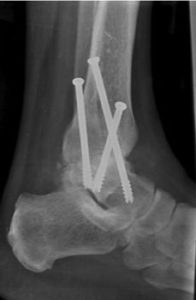

Een artrodese van de enkel is dus het vastzetten van het enkelgewicht. Bij dit vastzetten wordt het scheenbeen (de tibia), het sprongbeen (de talus) en vaak ook het kuitbeen (de fibula) aan elkaar vastgezet met schroeven. Door deze fixatie zal het lichaam deze botdelen laten vergroeien. Het gevolg is dus een enkel met beperkte beweging (mobiliteit).